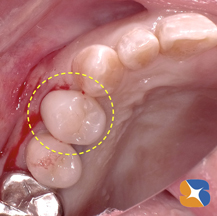

左図は、皮を縫い合わせる直前の状態です。このように、「CT」「点滴」「採血」「遠心分離機」「フィブリノーゲン」「動物由来ではない人工骨」を駆使して、インプラント治療への準備が整いました。半年後、同部の成熟が楽しみです。お疲れ様でした。